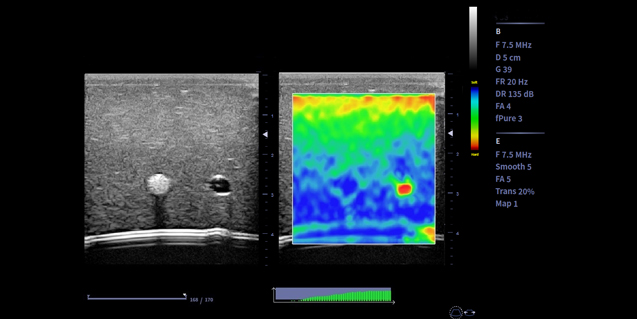

微血流成像

传统